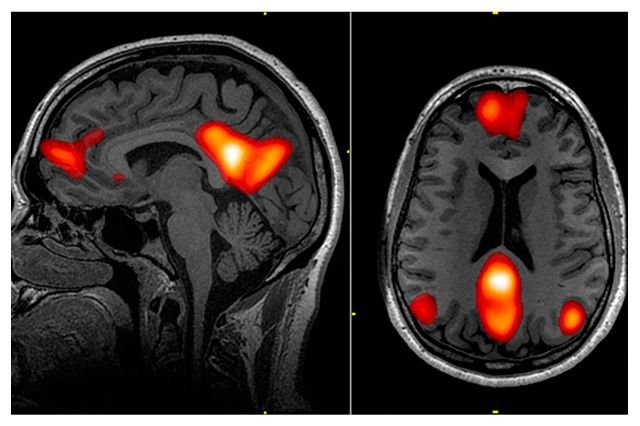

Obsessive-Compulsive Disorder has always revolved around the uneasy dance between intrusive thoughts and the compulsions we use to manage them. Traditionally, these compulsions showed up as repeated handwashing, checking locks, or arranging objects. Today, in an era of AI, instant information, and 24/7 connectivity, the landscape is evolving in subtle but profound ways. For some, compulsions now hide behind screens, chatbots, and search engines—turning devices meant to simplify life into catalysts for anxiety.